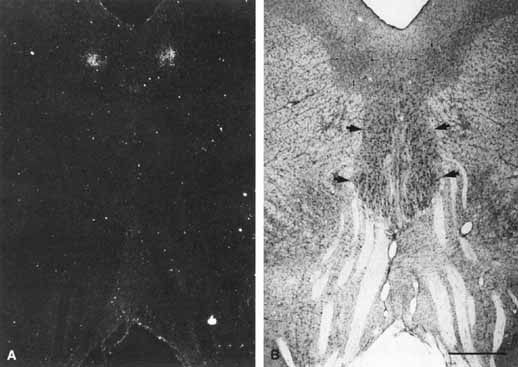

The organization of the oculomotor nuclear complex in the mesencephalon (midbrain) depicted by Warwick15 in 1953 and Jampel and Mindel16 in 1967 was modified by Burde and Loewy17 and Burde,14 recognizing the anterior median nucleus rostrally and accessory cell columns caudally. The anteromedian nucleus is the source of special visceral efferent motor axons to the iris sphincter and ciliary musculature. This dorsal cell mass may be subdivided into a rostral portion associated with accommodation, a caudal portion—the stimulation of which produces pupil constriction, and a midportion associated with both accommodation and constriction. Direct input to the iris sphincter and ciliary body may also be provided by the nucleus of Perlia.10,17 The pretectal olivary nuclei receive direct retinal input and, in turn, provide direct input to the Edinger–Westphal nucleus. The exact location of the Edinger–Westphal nucleus in humans is not known. Kourouyan and Horton18 injected tritiated H-proline into macaque monkey eyes and found the primary pretectal retinal projections terminating in the olivary nuclei, ipsilaterally and contralaterally. The label for the Edinger–Westphal nucleus was found bilaterally in the midbrain, ventral to the cerebral aqueduct, in the central gray matter, in well-defined columns, corresponding to an area termed the lateral visceral column in the classic literature (Fig. 4). Using multiple markers, including wheat germ agglutin, May and Fratkin19 have further isolated the Edinger-Westphal nucleus in the macaque monkey and deduced that it is comprised of a solitary column of cells. Whether this is the case in humans remains to be determined.

Fig. 4 A. (Left) Transneuronal autoradiographic label in the Edinger–Westphal nuclei, seems bilaterally adjacent to the midline, ventral to the cerebral aqueduct. B. (Right) The label seen in A corresponds on each side to the fairly distinct cell group (thin arrows), the lateral visceral cell column of the Edinger–Westphal nucleus, shown in a Nissl-counterstained section. The somatic subnuclei of the oculomotor complex (thick arrows) contain larger nuclei. Fascicles from the oculomotor complex are seen streaming inferiorly toward the interpeduncular fossa. Scale bar = 1 mm. (Reprinted with permission from Kourouvan HD, Horton JC: Transneuronal retinal input to the primate Edinger–Westphal nucleus. J Comp Neurol 381:68, 1997)